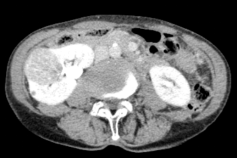

广泛开展腹腔镜下肾癌根治术、肾盂癌根治术、肾部分切除术、肾肿瘤剜除术、肾上腺肿瘤切除术、肾盂输尿管成形术、肾囊肿去顶减压术、输尿管上段切开取石术等。全腔镜下进行,创伤小、恢复快。

腹腔镜肾肿瘤剜除术(保肾) 腹腔镜肾癌根治术 腹腔镜肾盂癌根治术